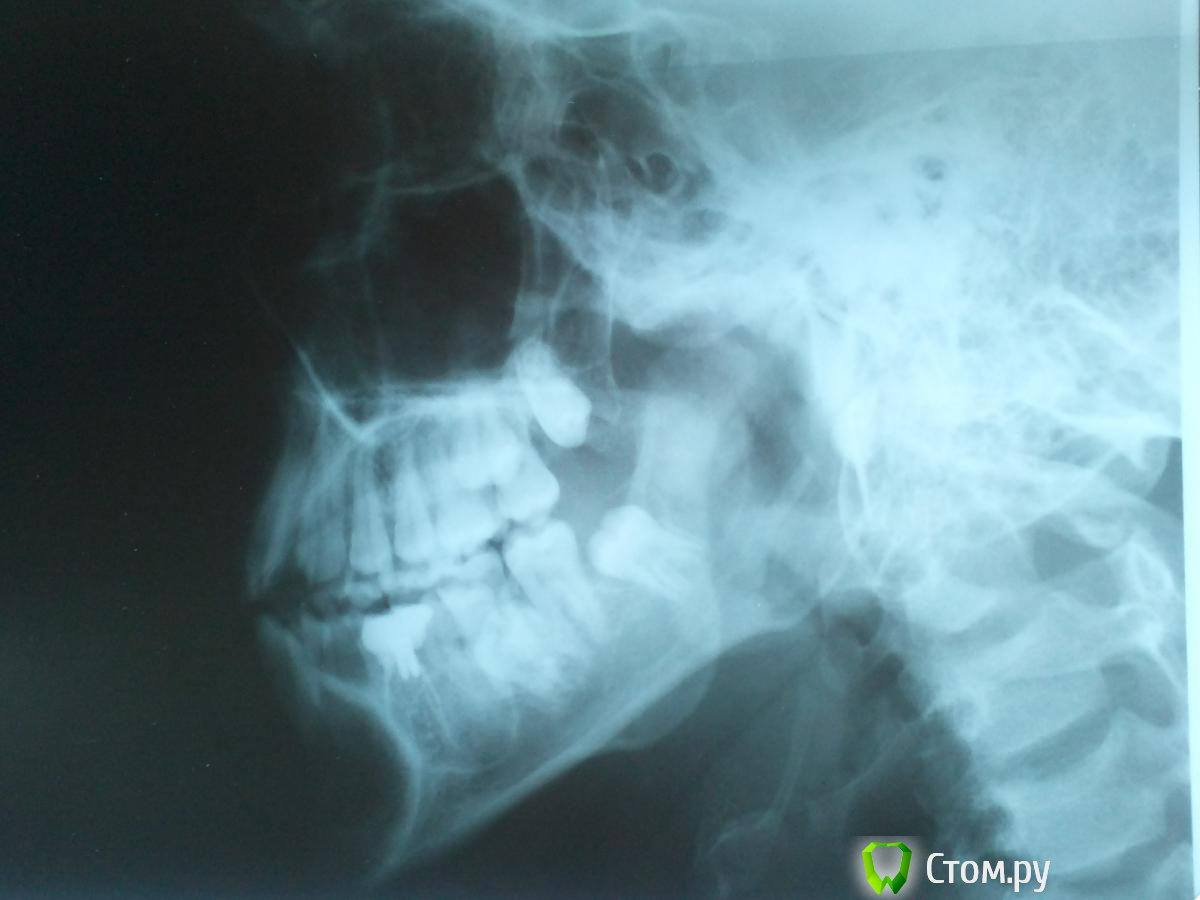

Александр1996 Опубликовано 29 мая, 2014 Автор Поделиться Опубликовано 29 мая, 2014 Что бы это могло быть ? Вот только вернулся от другого врача , решили мне вскрыть 35 зуб ( самый больнющий) Поставили 3 укола не морозило , сверлили и чистили канал считай на живую , вышло немного жидкости и сукровица ,сейчас уже такая боль не ощущается , канал оставили открытым , полоскать сказали чтобы прочистить его , вот Ссылка на комментарий

Александр1996 Опубликовано 29 мая, 2014 Автор Поделиться Опубликовано 29 мая, 2014 Что бы это могло быть ? Вот только вернулся от другого врача , решили мне вскрыть 35 зуб ( самый больнющий) Поставили 3 укола не морозило , сверлили и чистили канал считай на живую , вышло немного жидкости и сукровица ,сейчас уже такая боль не ощущается , канал оставили открытым , полоскать сказали чтобы прочистить его , вот Вот ещё 1 снимок тоже 5 зуба Ссылка на комментарий

faity Опубликовано 30 мая, 2014 Поделиться Опубликовано 30 мая, 2014 Вот ещё 1 снимок тоже 5 зуба удалять зубы мудрости, пролечивать 3.5, делать КТ, похоже на ростовую кисту, все лечится если лечить Ссылка на комментарий